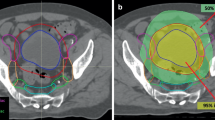

In our study, gross tumor volume (GTV) equals the prostate since the tumor burden from MRI and PSMA-PET was not available for all patients. Safety margins comprised 3 mm from GTV to clinical target volume (CTV) and 5 mm from CTV to planning target volume (PTV). The larger PTV includes prostate and seminal vesicle, whereas the SIB-PTV only contained the prostate without the seminal vesicle to protect the rectum as shown in Fig. 1 [20]. The mean SIB-PTV for the prostate gland without margins was 148.0 cm3 for the HRT group and 184.8 cm3 for the CRT group. Furthermore, the delivered mean dose to the urinary bladder (rectum) for the HRT arm was 24.8 Gy (27.7 Gy) and 34.6 Gy (37.4 Gy) for the CRT arm. The overall treatment time differed strongly between the groups: for the CRT group it amounted to up to over 55 days on average, whereas it lasted only 29 days for the HRT group.

Reduction of planning target volume (PTV) of “prostate and proximal vesicle” (green) to PTV of “simultaneous integrated boost (SIB) prostate without proximal vesicle” (orange). Delineation of rectum as a region of interest is not included in the graphic to improve visualization of the relevant anatomic features